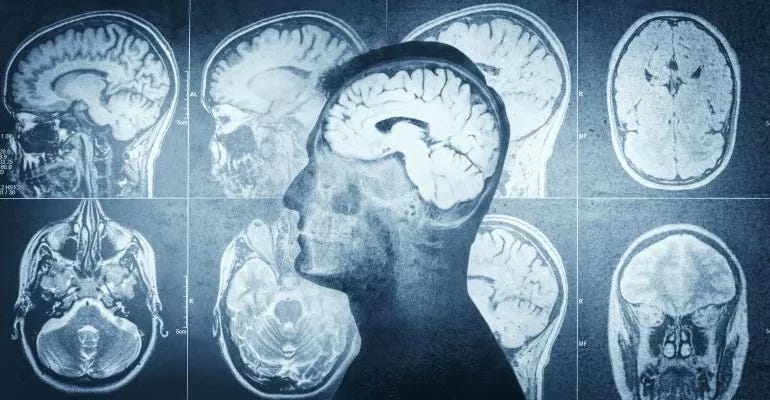

Radiology in today’s world has become so vital that doctors cannot manage patients without diagnostic imaging. While the physical exam has not changed much in 300 years, imaging has changed dramatically in just a quarter century. In fact, it can be said that diagnostic imaging has revolutionised medicine and is at its core today.

Doctors often rely on radiology test results to determine patients’ diagnosis and the course of their treatments. It has clearly transformed patient care to the extent that many refer to the CT scanner, or computerised tomography as “truth”. The history of radiology dates back to 1885 with the discovery of X-rays by German physicist Wilhelm Conrad Röntgen which won him the Nobel Prize in Physics in 1901. Subsequently, in 1946, nuclear magnetic resonance (NMR) is discovered independently by Edward Purcell and Felix Bloch. The invention of the portable ultrasound machine was made by Ian Donald in 1955 together with Tom Brown that allowed healthcare providers to visualise a foetus in utero and eventually become a routine procedure in pregnancy as a means of monitoring the development and health of the foetus.

The first PET scan is built by James Robertson in 1961, which is a valuable research tool to learn and enhance our knowledge of the normal human brain, heart function and support drug development. In 1972, Godfrey Hounsfield developed the first clinical prototype of CT scanner wherein a rotating X-ray tube and a row of detectors placed in a gantry produces cross-sectional images of a body. The PET-CT scanner, attributed to David Townsend and Ronald Nutt, is named by TIME magazine as the medical invention of the year in 2000. Talking about its uses and applicability, interventional radiology (IR) is a very recent addition to medicine. It relies on the use of radiological image guidance to precisely target therapy.

Radiation therapy may be used to treat both benign and malignant tumours. It uses targeted energy to destroy cancer cells, shrink tumours and/or alleviate certain cancer-related symptoms. Truly, radiology has come a long way since its inception from humbling image production with glass photographic plates to high-resolution digital modalities that harness cutting-edge technologies, medical imaging has transformed medicine and continues to revolutionise patient care delivery.